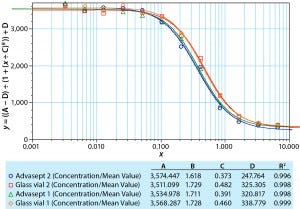

Figure 1: Dose-response curve for model MAb formulation

Potency: We used ultraviolet absorption (280 nm) and an activity assay to examine potency of the MAb before and after filling, as well as after nine months of storage at 5 °C (Table 1). The UV data indicate no apparent change in potency for both vial formats when tested before and after filling, and after nine months of storage at 5 °C both were within target range.

We also determined potency using a responsive cell line in a complement- dependent cytotoxic assay with a fluorescence read-out. Figure 1 compares a dilution series generated with a standard, the MAb formulation in glass, and the same formulation in an Advasept vial. These activity data show comparable potency values for the formulations in glass and Advasept vials after nine months of storage at 5 °C (all data not included).